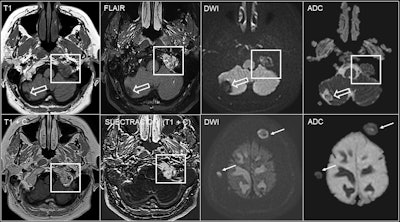

Bone metastases may present as diffuse bone involvement or focal lesions, where the hyperintense signal from fatty marrow on T1-weighted imaging (T1WI) sequences without fat suppression is replaced by a hypointense lesion. Lytic bone metastases show restriction in diffusion-weighted imaging (DWI) -- especially of breast and lung cancer origin -- but DWI is not useful for prostate bone metastases. Bone metastases show variable contrast enhancement, and postcontrast sequences allow the assessment of whether there is associated dural invasion.

“Use fat saturation pulses when obtaining postcontrast T1WI,” they recommended, adding that subtraction sequences may also be helpful.

60-year-old woman with breast cancer and bone metastases in the left occipital condyle (square) showing a hypointense focal lesion on T1 sequences without contrast, hyperintense signal on FLAIR sequences and diffusion restriction. Contrast enhancement can be seen on postcontrast 3D T1-weighted sequences, where subtraction sequences may be helpful if fat suppression has not been performed. There is also a cavernoma (empty arrow) in the right cerebellar hemisphere and other bone metastases with diffusion restriction in the calvarium (arrows).